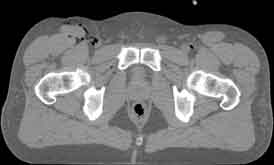

Visible Human male: Sectio transversalis 1900

CT

NMR

Pd                          / T2 \                         T1